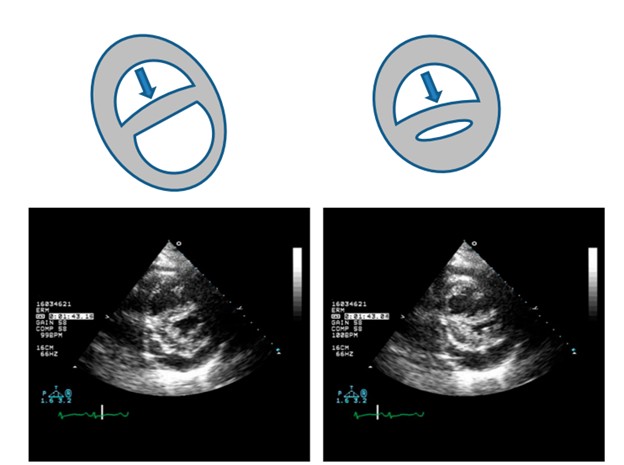

Siêu âm tim là thăm dò không xâm giúp đánh giá nhanh chóng kích thước TP, hình dạng và sự di chuyển của vách liên thất (VLT). Đường kính TP / TT> 1, kèm theo thất trái mất dạng hình cầu (dấu hiệu chữ D) là bằng chứng về sự gia tăng ALĐMP [7]. Có thể thấy hình ảnh vách liên thất phẳng (đi ngang) thì tâm trương xảy ra khi có quá tải về thể tích (ví dụ trong các trường hợp có shunt trái –phải), hoặc VLT phẳng (đi ngang) thì tâm thu khi có quá tải về áp lực, hoặc phẳng ( đi ngang) cả 2 thì tâm thu và tâm trường khi có TAĐMP nặng (gồm cả hội chứng Eisenmenger).

Hình 6. Sự phụ thuộc lẫn nhau giữa 2 tâm thất trong suy tim phải.

Sự gia tăng bệnh lý áp lực làm đầy thất phải làm ảnh hưởng đến di chuyển của vách liên thất. Do thất phải bị giới hạn bởi màng ngoài tim (mũi tên), tăng áp lực trong buồng thất phải (RV)sẽ dẫn đến sự dịch chuyển về bên trái của vách liên thất, làm thay đổi thái của thất trái (LV). Những thay đổi này góp phần làm giảm cung lượng tim do giảm độ nhạy của TT, giảm tiền gánh và giảm độ co giãn của thất trái, và cũng làm giảm đổ đầy tâm trương TT. Dịch chuyển về bên trái do hạn chế màng ngoài tim khi tăng áp lực cuối tâm trương TP và làm biến dạng mối quan hệ về hình thái bình thường giữa 2 tâm thất cũng làm suy giảm chức năng co bóp TP.(Haddad et al 2008, AHA ).